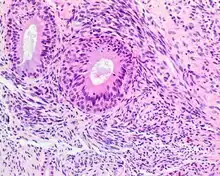

Hematoxylin and eosin stained image of a biphenotypic sinonasal sarcoma

• Infiltrative, highly cellular spindled cell neoplasm is poorly circumscribed and unencapsulated. Bone destruction or invasion is common. The cells show medium to long fascicles (nerve fibers), with a herringbone pattern. The cells are remarkably uniform with elongated nuclei. Delicate strands of intercellular collagen without ropy or dense deposition are seen. A very characteristic concurrent surface-type respiratory epithelial proliferation is found from the surface or in small cystic spaces around the cancer cells, often forming glands. The background may have a rich vascularity and usually has a small number of scattered lymphocytes. Extra growths or mitoses are rare, while necrosis, ulceration, and hemorrhage are usually absent.